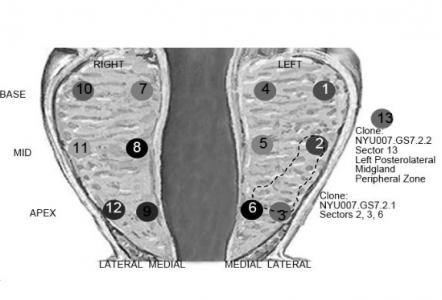

La méthode ici testée, qui vient en complément de la biopsie pré-chirurgicale standard consiste en son analyse plus approfondie. L'équipe séquence les génomes de plusieurs centaines de cellules individuelles prélevées sur les noyaux de biopsie de chaque patient, à la recherche de certaines variations de nombre de copies (CNVs : copy-number variations) puis, grâce à un programme informatique, les cellules qui présentent les mêmes irrégularités ou cellules « clonales » qui caractérisent la tumeur. La méthode assigne ensuite un score à chaque noyau de biopsie, qui correspond au taux de cellules clonales et permet ainsi d’évaluer dans quelle mesure ces cellules sont dispersées dans la prostate. La méthode permet d’aboutir, selon cette étude pilote, à des évaluations de tumeurs plus proches d’un diagnostic post-chirurgical reflétant exactement la maladie réelle, que la biopsie pré-chirurgicale.